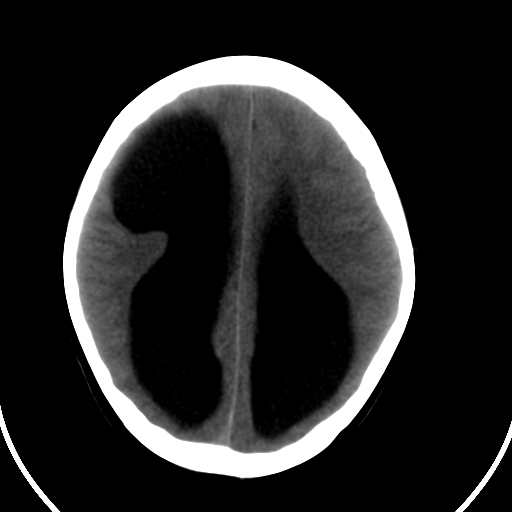

男,11岁

右额叶单发近圆形低密度影,周边光滑,与侧脑室相通,考虑为孔洞脑并阻塞性脑积水。

右额叶内见一边界清楚,脑脊液密度的囊腔,无灰质内衬,并与脑室相通,四室以上脑室系统高度扩张。诊断:先天性脑穿通畸形伴梗阻性脑积水

需要与脑裂畸形鉴别:可见单侧或双侧衬有皮层的脑裂伸入额顶叶的白质内并与脑室相通

脑穿通畸形并梗阻性脑积水.

脑穿通畸形囊肿脑积水